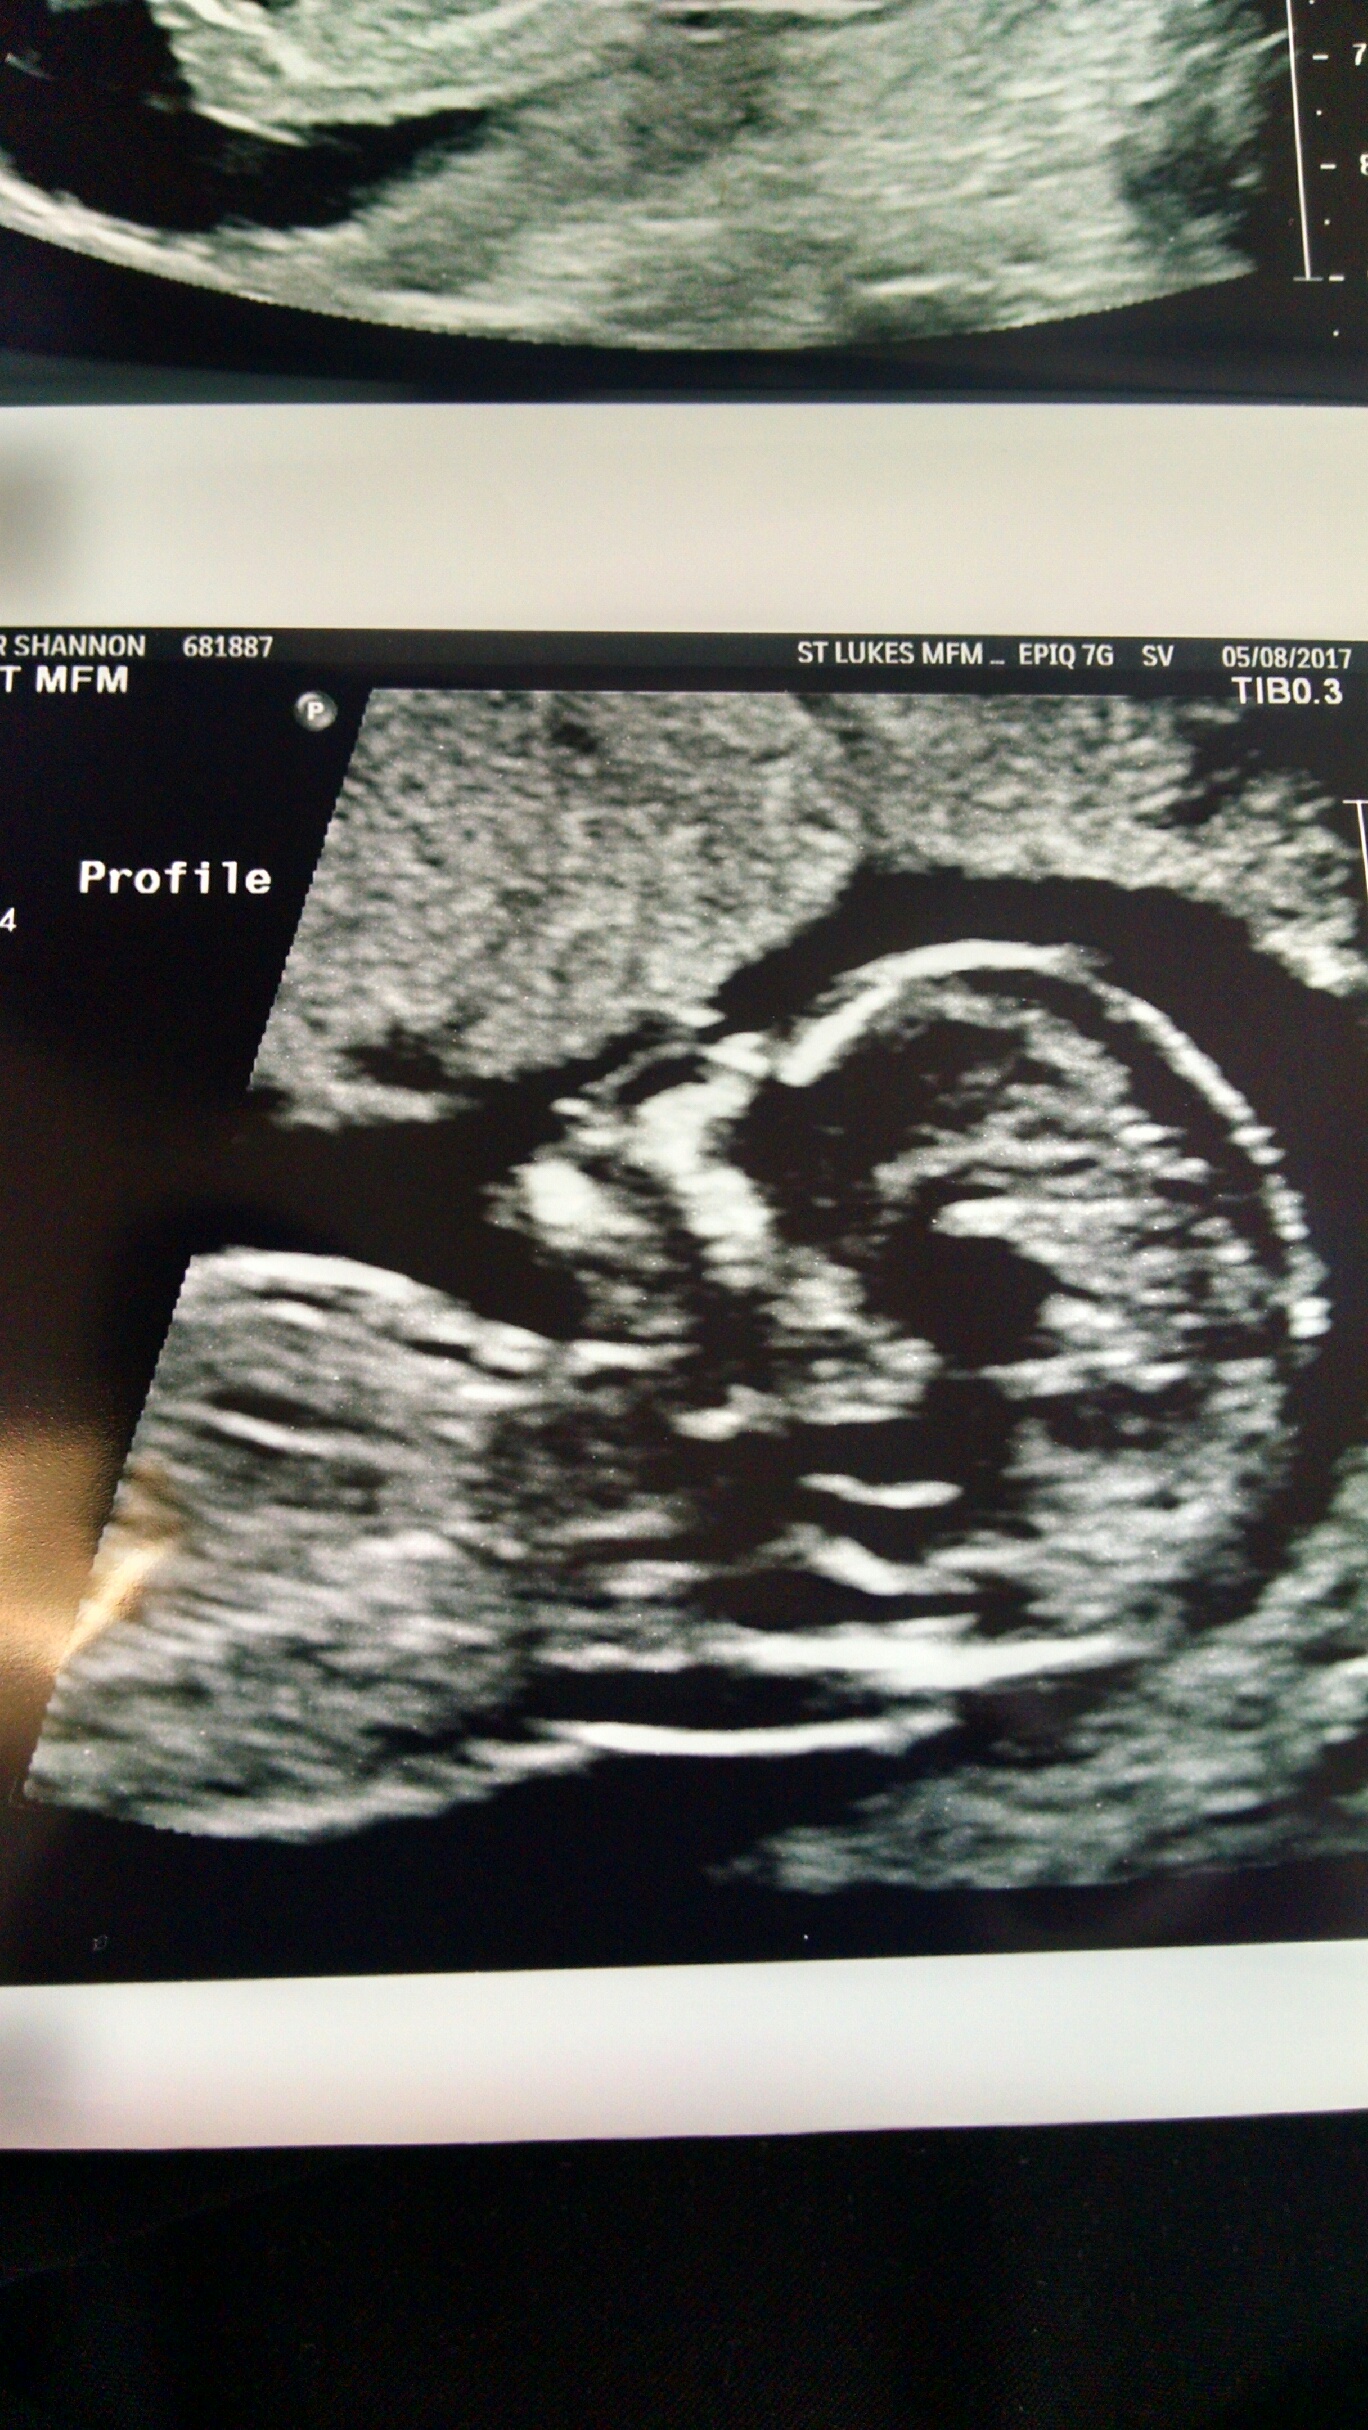

I am not sure if this is a nub or not. But here are my 13w scan pics. Any and all guesses welcome. These are all the pics I got and no video. :)

Attachment 36129

Cute baby! These aren't the greatest for nub guessing. It looks like the cord in the top pic. The legs are obscuring/altering the nub. I *think* the nub is slightly below the cord but not enough is seen for me to make a guess. Skull looks very girlie though not reliable.

Baba's leg is hiding the nub. Super cutie though! :heart: did you see any clues during the scan? X